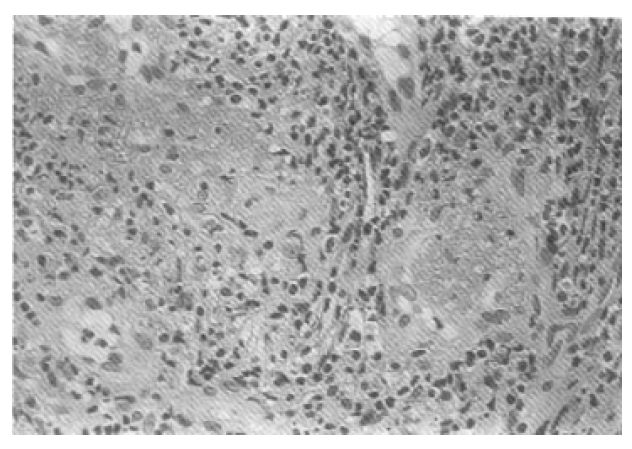

Fig. 2.

Nasal septal biopsy shows granulomatous inflammtion with central neutrophilic infiltration and surrounding zone of histiocytes in cental area. The peripheral area shows dense lymphocytic infiltration(H & E stain, ×100)

Fig. 3.

Nasal septal biopsy shows the small vessels’ wall diffusely infiltrated with leukocytes, perivascular inflammation(H & E stain, ×400)